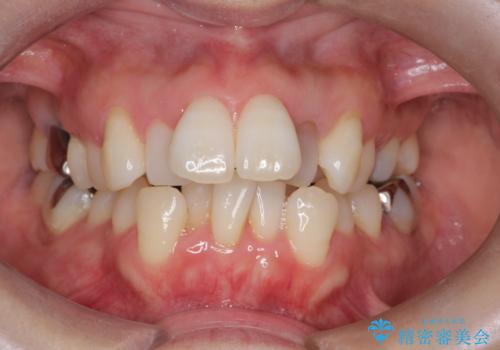

八重歯を抜歯矯正でスッキリと メタルブラケットでの矯正治療

担当医 藤巻太一朗